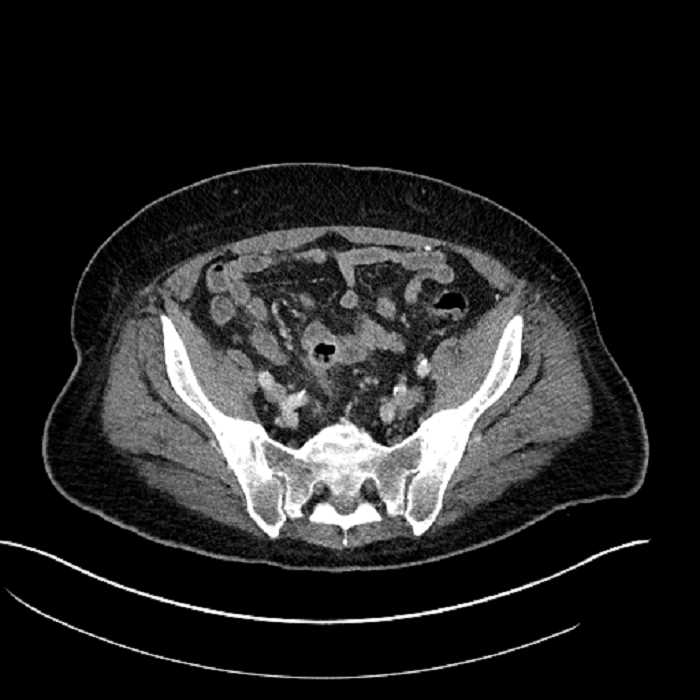

• Mild mural thickening of a segment of the sigmoid colon with adjacent fat stranding and a 1.5 cm fluid and gas collection along the tip of an inflamed diverticulum

• Loss of the normal fat plane between this collection and adjacent loops of small bowel, which demonstrate mural thickening

• No bowel obstruction

Acute sigmoid diverticulitis complicated by a small contained perforation and a large abscess in the right hepatic lobe. Additional small subcapsular abscesses along the anterior margin of the left hepatic lobe.

Additionally, loss of the normal fat plane between the peridiverticular collection and adjacent thickened loops of small bowel raises the potential for an enterocolonic fistula.

Hepatic abscess showing the double target sign with low density internally surrounded by a thin inner enhancing rim (red arrow) and ill-defined outer low density rim (yellow arrow). Blue arrow indicates an internal septation. Red arrows: additional smaller subcapsular abscesses. Red arrow: focal contained perforation associated with diverticulitis.